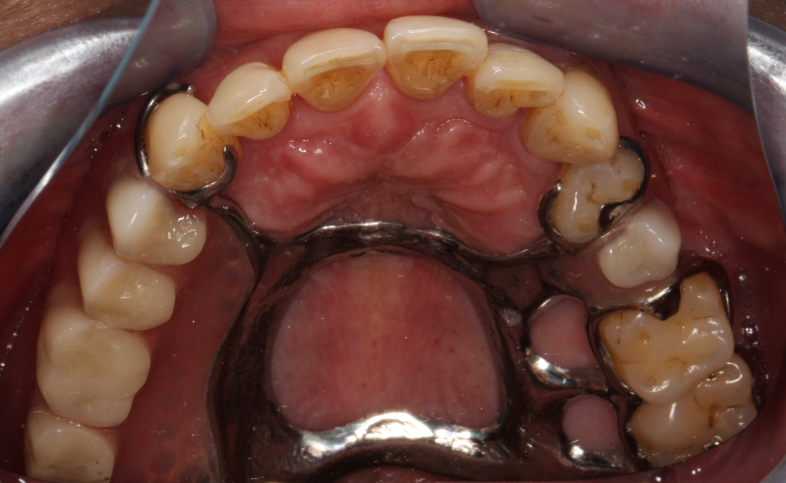

三、种植义齿:目前最理想的“仿生方案”

什么是种植牙?

它被誉为“人类的第三副牙齿”。其原理并非简单地在牙龈上做假牙,而是在牙槽骨内植入一个纯钛的“人工牙根”(即种植体),待其与骨骼牢固结合后,再在上面安装牙冠。

图3.种植义齿修复示意图

它的核心特点:

优点:

1.  不伤邻牙: 最大程度地保护了您的健康邻牙,无需磨损任何其他牙齿。

2.  功能强大: 能恢复90%以上的咀嚼力,咀嚼感受最接近真牙。

3.  舒适美观: 无异物感,外形、色泽、通透度都可媲美天然牙。

4.  保护牙槽骨: 咀嚼力通过种植体直接传递至牙槽骨,能有效防止缺牙区域的牙槽骨萎缩。

5.  长期耐用: 在维护得当的情况下,是目前使用寿命最长的修复方式。

缺点:

1.  治疗周期长:从植入种植体到戴上牙冠,通常需要3-6个月甚至更久,以供骨结合。

2  门槛较高: 对患者的全身健康状况(如未受控制的糖尿病、严重心脏病)、口腔局部条件(如牙槽骨的高度和密度)以及口腔卫生习惯都有严格要求。

3.  需要微创手术: 需要接受一次植入手术,虽然是小手术,但仍存在极低的感染和失败风险。

最适合人群: 全身健康状况良好,牙槽骨条件许可,追求最佳修复效果,并愿意为长期健康投资的患者。